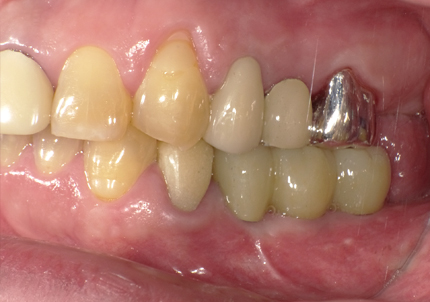

11.口腔内写真(2025年6月)

右下2本初診より9年経過、左下3本埋入後4年経過、ともに経過良好。